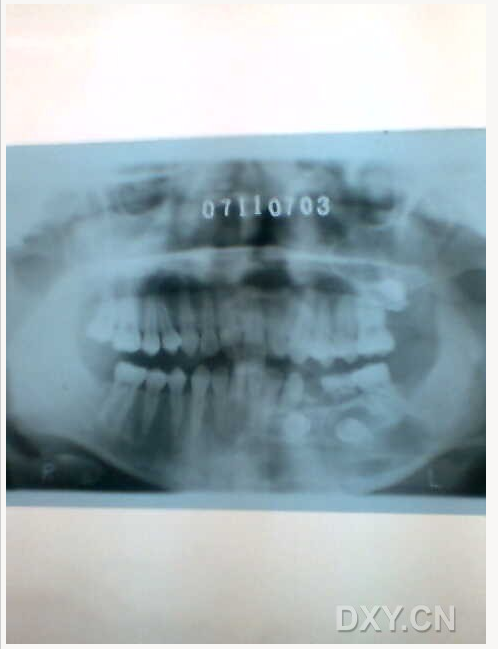

頜骨骨折